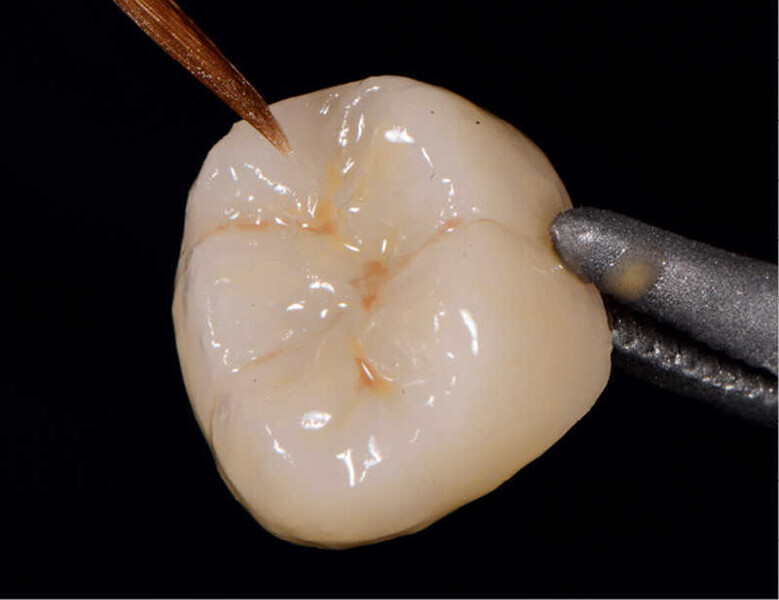

Figs. 12a y 12b. Vista final lateral y oclusal.